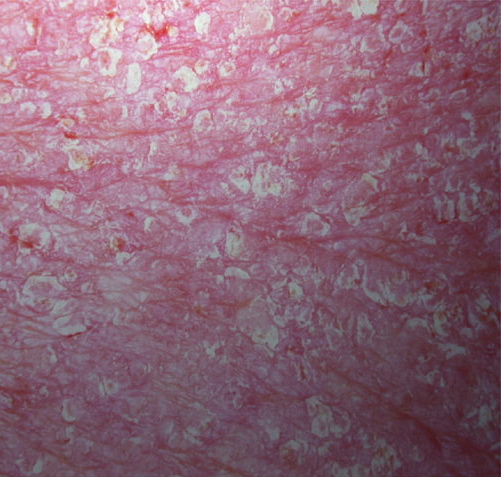

Psoriasis_erythrodermic = الأحمرية الصدفية